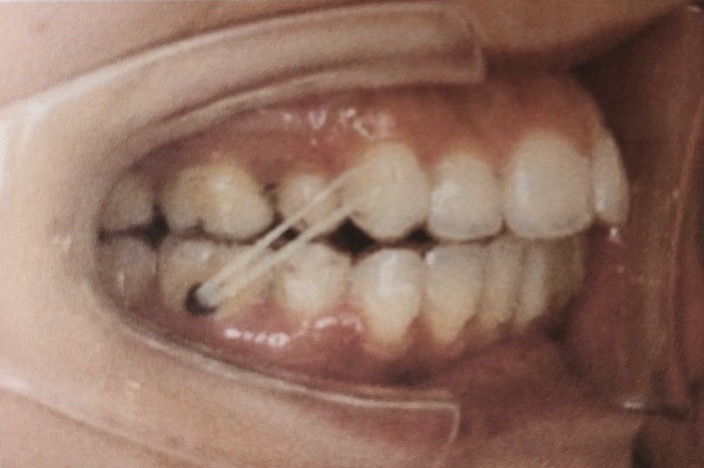

ボタンとインビザラインにエラスティックゴムをかけます。(下記写真↓)

この写真をみると上下前歯が噛み合ってなく少し前歯に隙間があるのが分かると思います。

エラスティックゴムをかけた事によって、この上下の隙間を無くしてくれる働きがあります。

エラスティックゴムはインビザラインによる歯の動きを助けたり、反作用の力を抑える効果があります。